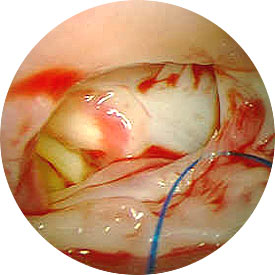

Surgical Technique

Timing of complete repair of Tetralogy of Fallot varies. Early palliation for hypercyanotic spells or severe cyanosis can be provided by a modified Blalock-Taussig shunt. Total repair of Tetralogy of Fallot requires cardiopulmonary bypass and aortic cross-clamping. Repair of this lesion can be approached via either a right atriotomy or a right ventriculotomy, depending on the degree and length of right ventricular outflow tract obstruction. Right ventricular obstruction is relieved first with resection of obstructive muscle. The ventricular septal defect is then closed with interrupted sutures. Pulmonary arterioplasty or pulmonary valvotomy is performed next, depending upon the individual needs of the patient. The integrity of the pulmonary valve annulus is spared whenever possible to maintain pulmonary valve competence. A patch across the pulmonary valve annulus (a transannular patch) is often required in order to adequately relieve right ventricular outflow tract obstruction. Following adequate rewarming, the patient is weaned from cardiopulmonary bypass. Transesophageal echocardiography is utilized to help assess adequacy of repair. Cardiopulmonary bypass time and aortic cross-clamp time required to complete repair are usually moderate in length.